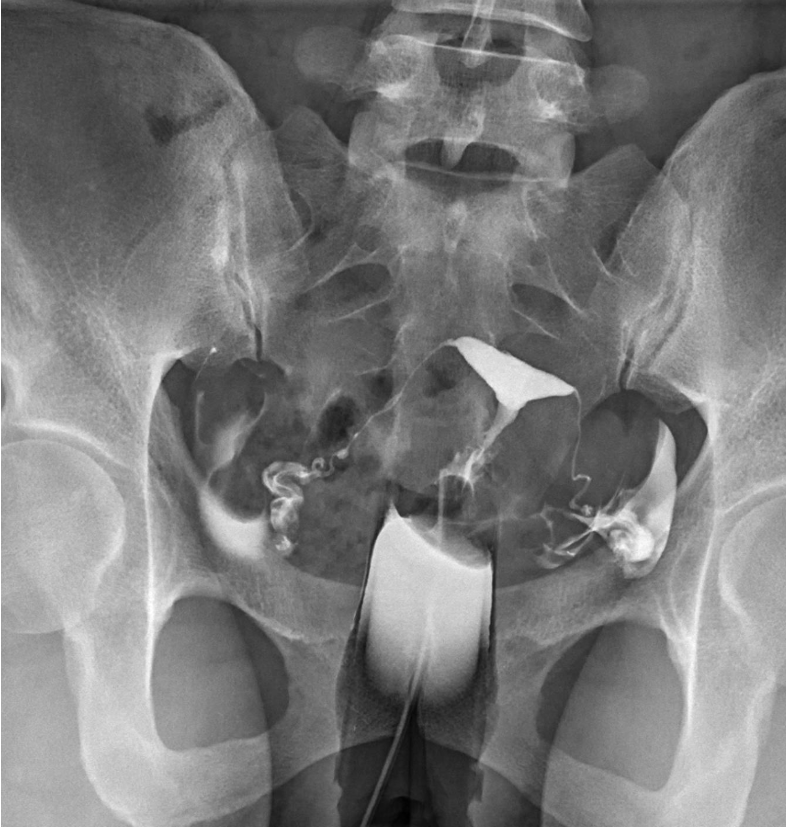

L’hystérosalpingographie ou hystérographie est un examen destiné à évaluer la perméabilité tubaire. Il est prescrit dans le cadre d'un bilan d'AMP (aide médicale à la procréation).

L’examen (15 minutes environ), se déroule en position allongée et immobile, sur le dos ou en position gynécologique. Un spéculum est positionné pour exposer le col. Un produit de contraste iodé est ensuite injecté permettant d'évaluer la perméabilité tubaire.